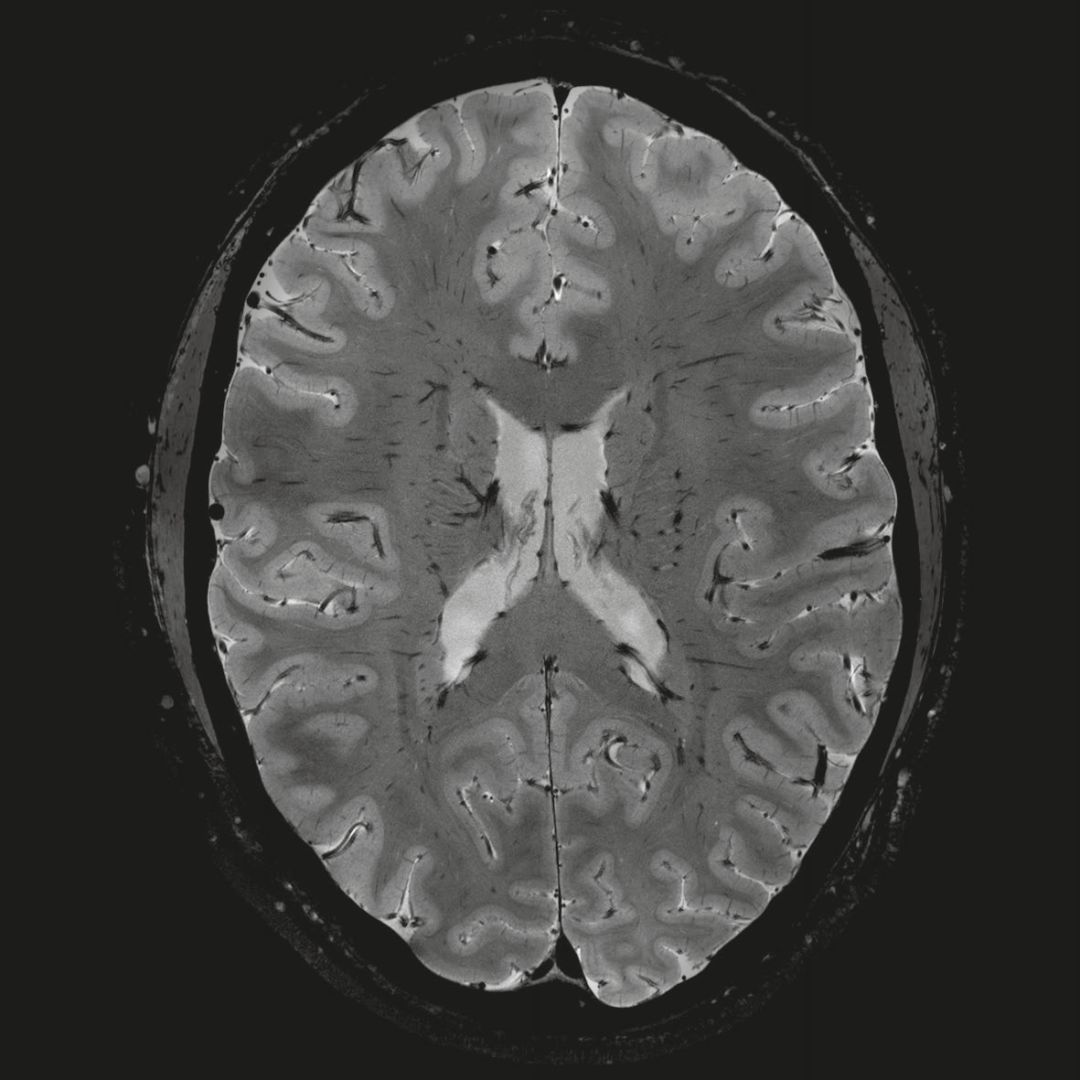

全球首臺臨床科研雙模7T磁共振MAGNETOM Terra亮相中國

在剛剛結(jié)束的China Med上,西門醫(yī)療首次在中國展出了首臺臨床科研雙模7T磁共振MAGNETOM Terra,大部分現(xiàn)場觀眾也是首次看到這臺號稱“全球首臺可用于臨床的7T磁共振”。

大家知道,傳統(tǒng)的臨床磁共振場強是1.5T和3T,而7T以上的磁共振場強被稱為超高場(UltraHigh Field),一直沒有用于臨床。

但近年來,西門子與科研機構(gòu)共同研究發(fā)現(xiàn),7T提供了數(shù)倍于傳統(tǒng)3T磁共振的信噪比和空間分辨率,在神經(jīng)、血管、腫瘤、骨關(guān)節(jié)等多個方面都會帶來全新的突破性進展。尤其是在目前常規(guī)影像設(shè)備難以診斷的神經(jīng)退行性疾病如阿茲海默氏病、帕金森病等疾病的發(fā)病機理、早期診斷、治療方案確定以及治療效果評估上,有著極大的潛力。

這款全新的7T MAGNETOM Terra 具有哪些亮點呢?

• 首先,全新設(shè)計的磁體

MAGNETOM Terra 使用了西門子牛津磁體公司全新設(shè)計的磁體系統(tǒng),該系統(tǒng)的指標(biāo)超越了過去25年超高場領(lǐng)域所有的產(chǎn)品。 Terra也因此成為全球唯一一款使用廠家原生磁體的7T系統(tǒng)。

全新7T磁體

新的磁體采用了獨特的設(shè)計和熱平衡材料,最大限度的減少了核心部件間相互作用;還具有更穩(wěn)定的結(jié)構(gòu),更高的磁體穩(wěn)定度、更佳的靜態(tài)磁場均勻度和動態(tài)磁場均勻度,從而為臨床帶來更高的圖像質(zhì)量。

最關(guān)鍵的是,對比傳統(tǒng)7T磁體,MAGNETOM Terra的重量減少了50%。這使得Terra相對于傳統(tǒng)7T磁共振,場地要求減少50%以上,安裝速度加快50%以上,為臨床的大規(guī)模應(yīng)用奠定了基礎(chǔ)。

• 其次,強勁的梯度系統(tǒng)

MAGNETOM Terra在業(yè)界首次實現(xiàn)了兩倍于傳統(tǒng)7T的超強梯度性能,實現(xiàn)超快速、超高效、超高分辨功能磁共振成像。如此高性能的梯度系統(tǒng)無論對于科研還是臨床都帶來了更多可能。

1毫米的各向同性分辨率DTI:神經(jīng)纖維束的交叉細節(jié)顯示

0.8毫米的各向同性分辨率:精確劃分灰質(zhì)和白質(zhì)

0.8毫米的各向同性分辨率:超精細的解剖細節(jié),例:小腦的精細結(jié)構(gòu)

• 第三,.業(yè)界最高的射頻系統(tǒng)

MAGNETOM Terra使用Tim 技術(shù),可以獲得超高通道數(shù)的獨立射頻數(shù)據(jù)接收能力,為臨床提供了更為強大的系統(tǒng)采集能力,數(shù)據(jù)采集能力達到傳統(tǒng)7T兩倍,帶來無窮的科研可能。

超精細的解剖細節(jié):T2對比

0.17 x 0.17 x 0.8毫米分辨率超高。

(TOF)300微米的各向同性分辨率顯示最小的血管

此外, MAGNETOM Terra也是全球首臺全部部件均由廠家SIEMENS原生設(shè)計、制造和提供后期維護的7T磁共振,在提供穩(wěn)定的系統(tǒng)性能的同時也為未來的系統(tǒng)安全性提供了充分的保障。

目前,MAGNETOM Terra已于2017年順利取得FDA 和CE認證,在歐洲和美國已經(jīng)可正式用于臨床!

中國目前也安裝了兩臺可應(yīng)用于人體的7T磁共振,均來自SIEMENS,分別位于中國科學(xué)院生物物理研究所和浙江大學(xué)。

西門子在超高場領(lǐng)域已深耕20年以上,全球超過70%的7T磁共振來自于西門子,到目前為止,如果說7T還有少數(shù)廠家能夠提供的話,包括9.4T、10.5T、11.7T等在內(nèi)的超過7T的超高場磁共振系統(tǒng)則只有SIEMENS是全球唯一供應(yīng)商!